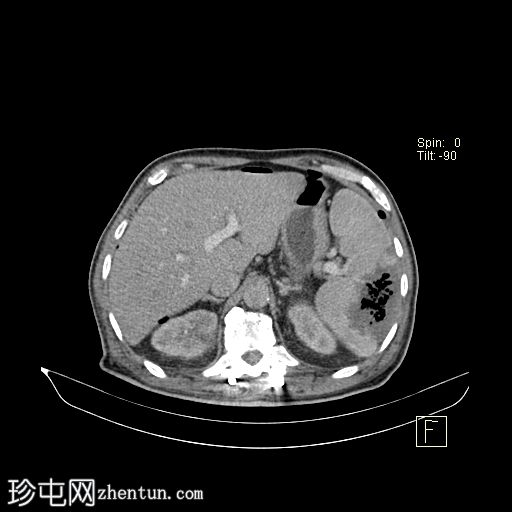

轴向C+门静脉期

脾脏肿大,可见一个边界不清的大型包膜下积液,内有多个大气泡,提示脓肿已延伸至腹腔,导致气腹。

左侧肾旁筋膜反应性增厚,伴有肾周脂肪条带。

左

肺

下叶可见一片实变或肺不张。